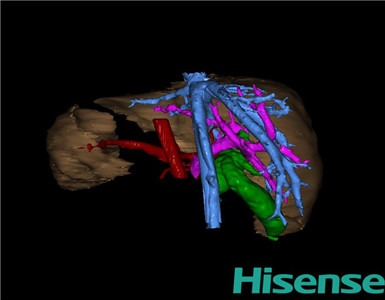

CT结果输入海信CAS系统后行3D重建及手术规划后,于2015-8-18全麻下行“胆总管囊肿切除+胆囊切除+胆总管-空肠吻合术”手术治疗:

将0.625mm双源薄层CT资料的静脉期和动脉期Dicom格式文件导入海信CAS系统。

通过调节窗宽窗位调整CT序号,对肝实质,胆囊,下腔静脉,肿瘤,肝动脉、门静脉及肝静脉等进行三维重建;系统自动计算肝脏体积。

术前三维重建:

重建图片